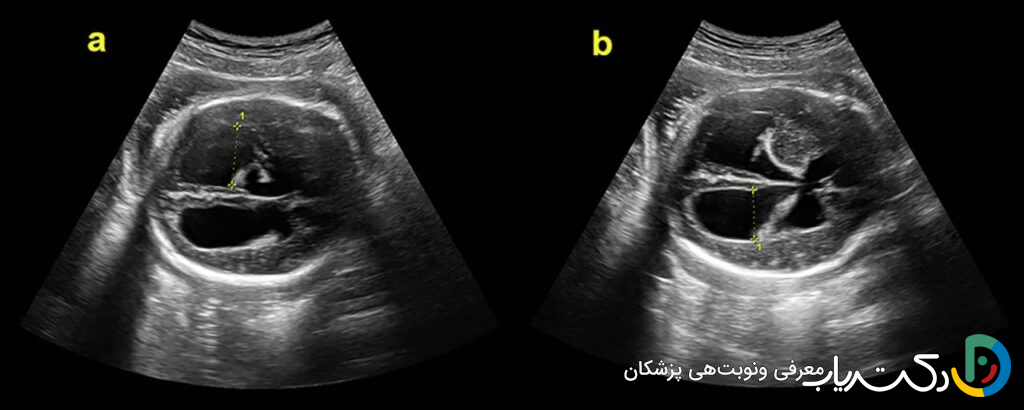

سونوگرافی: پنجرهای به سوی مغز جنین

در طول بارداری، چندین سونوگرافی برای بررسی رشد و سلامت جنین انجام میشود. در این اسکنها، رادیولوژیست یا متخصص پریناتولوژی ساختارهای مختلف بدن جنین، از جمله مغز را به دقت بررسی میکند. یکی از بخشهای استاندارد این ارزیابی، مشاهده و اندازهگیری ساختارهایی مانند بطنهای مغزی، مخچه، و سایر قسمتهای کلیدی سیستم عصبی مرکزی است.

معیارهای تشخیصی در سونوگرافی: اعداد چه میگویند؟

متخصصان برای تشخیص و طبقهبندی شدت بزرگی بطنها، عرض دهلیز بطنهای جانبی را اندازهگیری میکنند. این بخش از بطنها به راحتی قابل مشاهده و اندازهگیری است و اندازه آن در نیمه دوم بارداری تقریباً ثابت باقی میماند.

- وضعیت نرمال: اندازه بطن کمتر از ۱۰ میلیمتر طبیعی تلقی میشود.

- ونتیکولومگالی خفیف : اندازه بین ۱۰ تا ۱۵ میلیمتر. این وضعیت همیشه به معنای هیدروسفالی فعال نیست، اما یک یافته مهم است که نیازمند بررسیهای دقیقتر و پیگیریهای مکرر است.

- هیدروسفالی آشکار یا شدید : اندازه بزرگتر از ۱۵ میلیمتر به وضوح نشاندهنده هیدروسفالی است و معمولاً با پیشآگهی جدیتری همراه است.